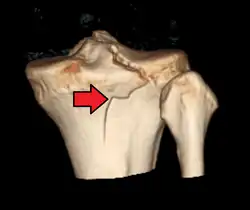

Studio delle ossa e delle articolazioni

Nonostante l'affermazione della risonanza magnetica nucleare per lo studio delle articolazioni abbia ridotto il campo di applicazione della tomografia computerizzata, la velocità di quest'ultima associata alla possibilità di ricostruzioni tridimensionali, hanno permesso alla TC di continuare a svolgere un ruolo di primo piano nella diagnosi di fratture complesse e nelle situazioni di urgenza.[62] Tra i distretti ossei più studiati in TC sempre più spesso vi è il bacino.[63] Nonostante tutto ciò, soprattutto per motivi radioprotezionistici e di costi, le fratture di più semplice diagnosi vengono valutate tramite radiografia tradizionale, relegando la tomografia per le situazioni dubbie e nei casi in cui non si abbia un paziente collaborante.[64][65]

Sicuramente l'elemento scheletrico (l'osso) è la porzione anatomica studiabile in TC con i migliori risultati, tuttavia, in particolari casi selezionati, l'utilizzo di mezzo di contrasto, sia per via endovenosa sia per iniezione intrarticolare, permette la visualizzazione degli elementi cartilaginei, muscolari e legamentosi. Talvolta la TC può essere utilizzata come supporto per procedure come la biopsia ossea e il trattamento degli osteomi.[66] La metodica può essere, inoltre, utilizzata anche per la diagnosi e la valutazione in corso di trattamento dell'osteoporosi.[67] |lingua=en Inoltre anche la colonna vertebrale, nonostante la risonanza magnetica sia considerata il gold standard per molte sue patologie, può essere studiata in TC, in particolare alla ricerca di ernia del disco, protrusioni, fratture o crolli vertebrali nonché patologie neoplastiche.[68] Le ricostruzioni sui vari piani dello spazio sono spesso indispensabili per una corretta diagnosi.[69][70]